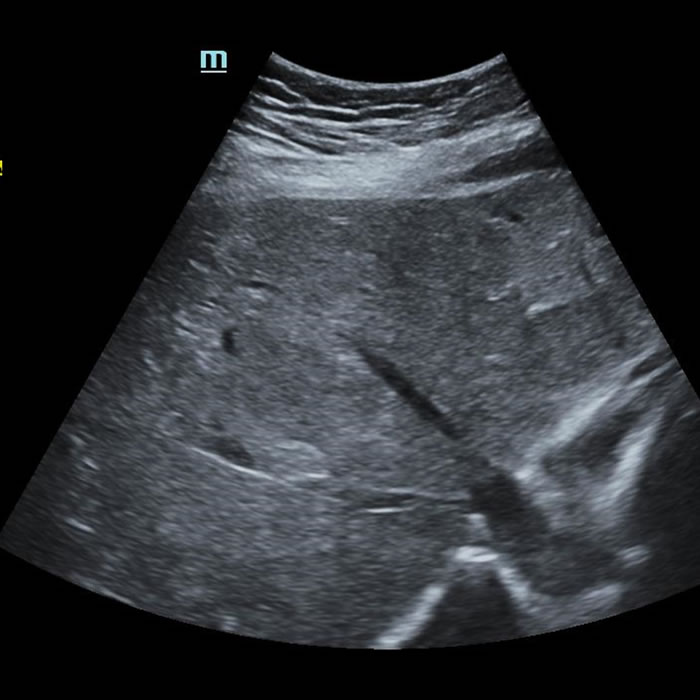

Mujer de 51 años. MC: anemia, náuseas, vómitos y diarrea.